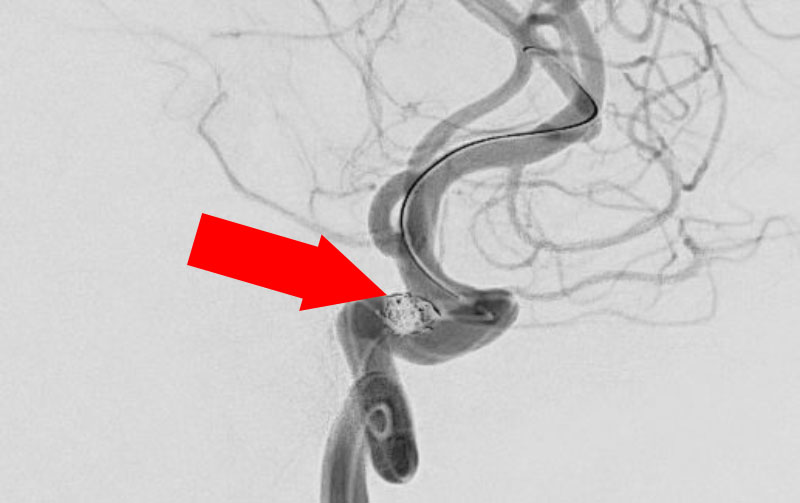

No.1600 手術前

No.1600 手術中

No.1600 手術後

くも膜下出血

脳底動脈瘤破裂

40代

救急外来